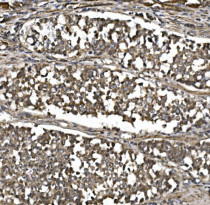

ARG43141 anti-CISD1 / mitoNEET antibody IHC-P image

Immunohistochemistry: Paraffin-embedded Human gastric cancer tissue. Antigen Retrieval: Heat mediation was performed in EDTA buffer (pH 8.0). The tissue section was blocked with 10% goat serum. The tissue section was then stained with ARG43141 anti-CISD1 / mitoNEET antibody at 2 µg/ml dilution, overnight at 4°C.